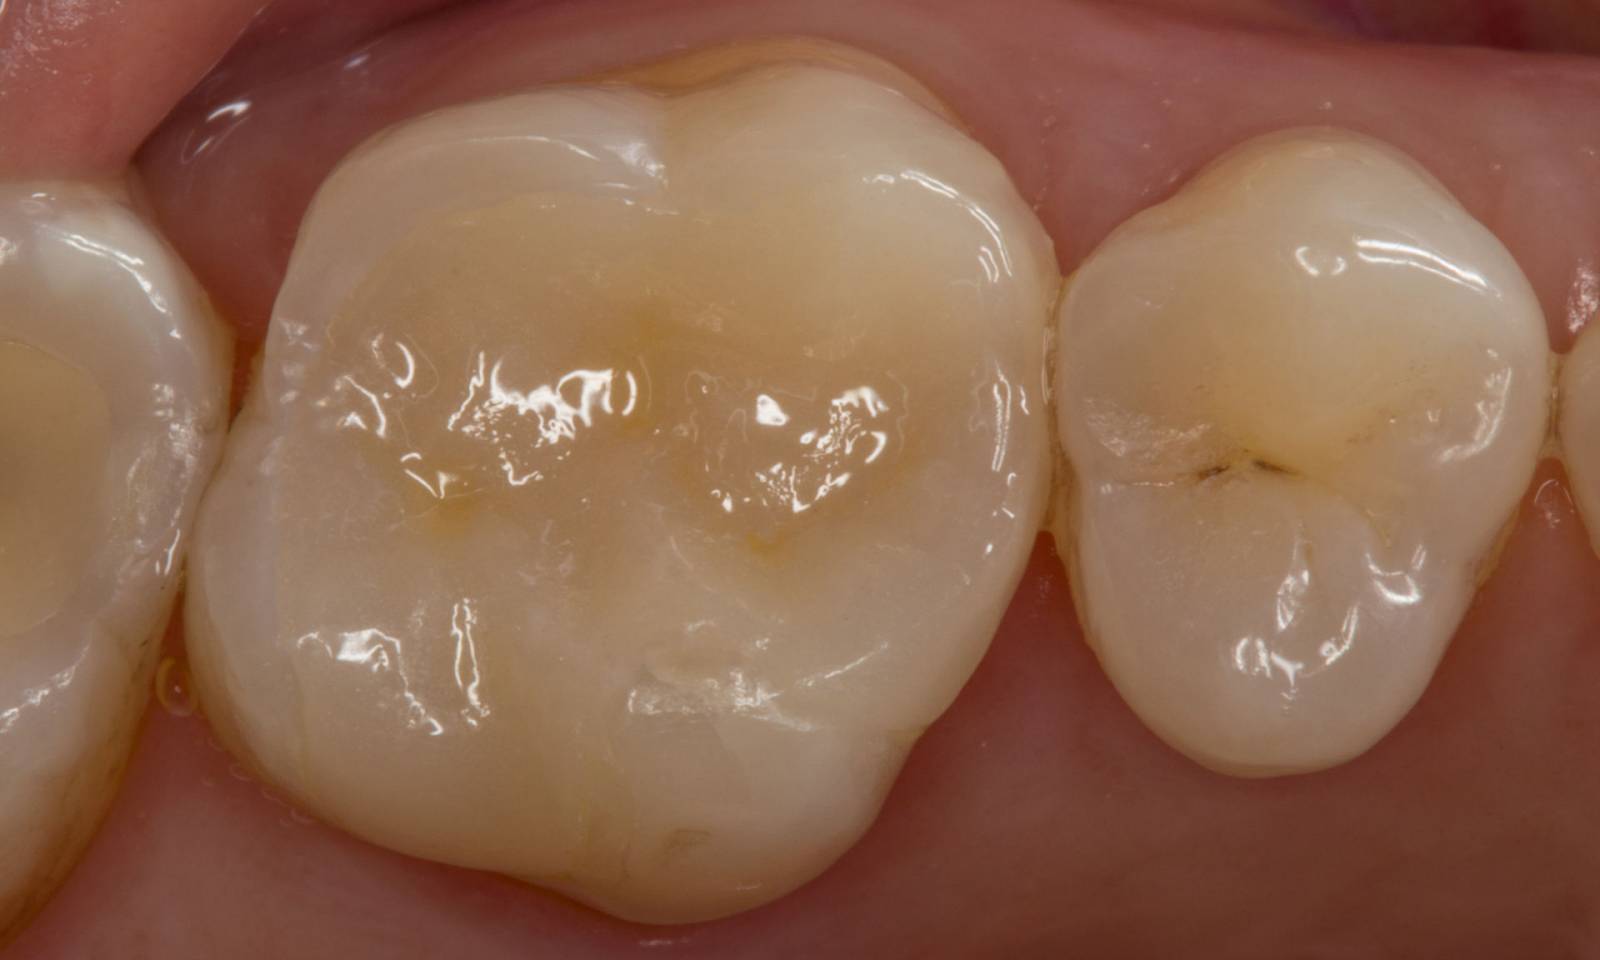

Before: Large insufficiency of the composite filling on tooth 16 with distal marginal ridge cracks, a lingual wall crack and distal recurrent decay.

After: Highly esthetic full-surface glass-ceramic crown.